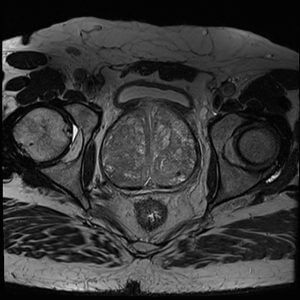

- Classification of clinically significant prostate cancer using raw MRI data. Self-supervised pre-training methods will be researched and implemented

Status: The IBIS-PRO project started in August 2024. Currently, data from the various hospital departments is being collected, manually checked and corrected if needed. In the meantime, research is done on masked autoencoders for feature extraction of raw MRI scans.